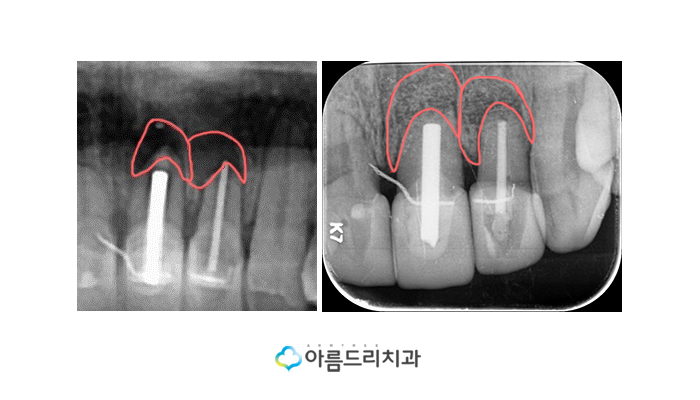

좌측이 치료전 사진으로 뿌리쪽에 염증이 있는 상태로

검게 보이는 것을 확인할 수 있으며 오른쪽이 수술을

마친 후 1개월째 사진인데 그 전과는 확연히 염증부위

(검은부분)이 사라지고 주변 잇몸의 색상과 동일하게

정상적으로 돌아오는 것을 확인하실 수 있습니다.